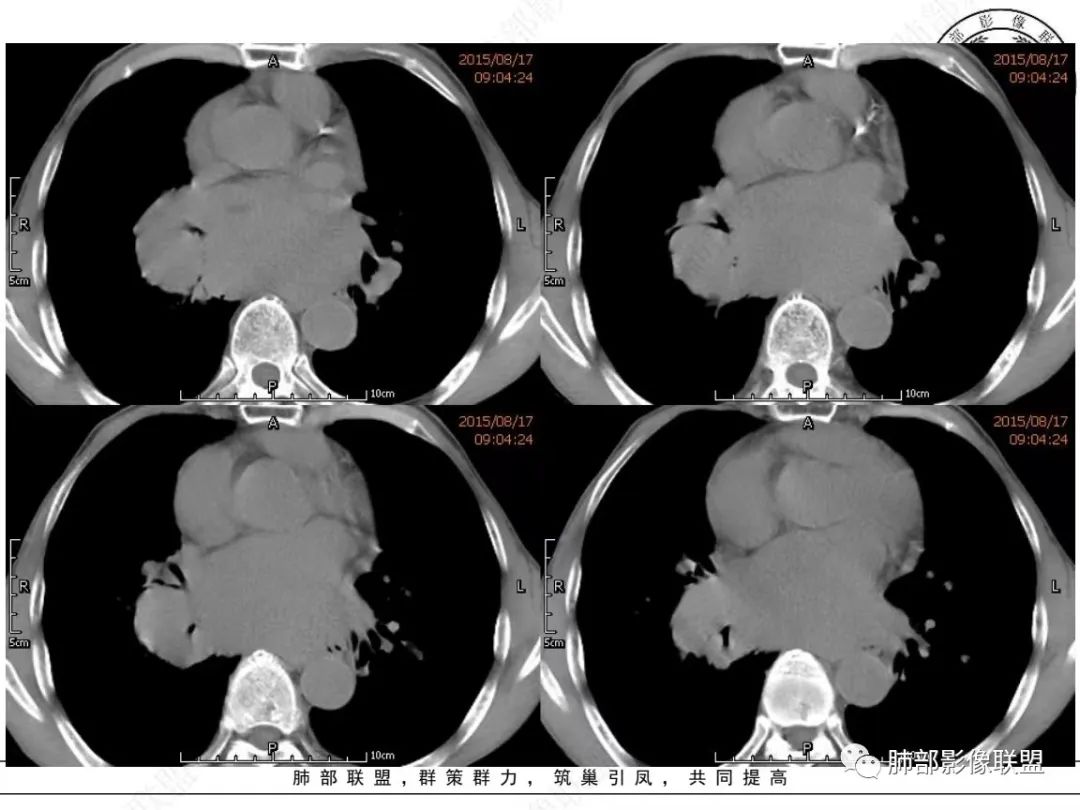

放射小白:老年男性,右侧肺门可见团块状占位包绕气管,气管受压变窄,纵隔见巨大团块状占位,另纵隔可见肿大淋巴结,增强肺门及纵隔肿块强化不明显,内部可见血管影,周围结构只是受压移位,另颌下淋巴结穿刺慢性淋巴结炎,首先考虑小细胞癌,鉴别淋巴瘤、结节病。

宇宙:右肺下叶小结节,右肺门及中后纵膈淋巴结肿大融合,强化均匀,主支气管、中间段及下叶支气管受压变窄,右下肺静脉受压变窄,考虑小细胞癌,鉴别淋巴瘤

丽:老年男性,纵隔及肺门多发肿大淋巴结,相互融合呈团块状,包绕支气管官腔,呈针尖样狭窄,增强后轻度强化,考虑小细胞肺癌

放射线:纵隔及肺门淋巴结肿大相互融合呈冰冻纵膈,支气管受压变窄呈针孔样,老年男性吸烟患者,考虑小细胞肺癌。

采莲:老年男性,有吸烟史,双颈部肿块,双肺纵隔淋巴结多发淋巴结肿大并融合成块,气管及右肺下叶支气管受压狭窄,考虑恶性,淋巴瘤可能,鉴别小细胞肺癌。

崔少钢:老年男性,有吸烟史,右肺下叶背段示小结节,纵隔、腋窝及右肺门淋巴结节肿大,气管受压狭窄,后纵隔软组织内示血管走行,考虑小细胞>淋巴瘤。

我只是邓较瘦:晨读老年男性,长期吸烟。右肺门、纵隔多发肿大淋巴结、融合成团块,中间支气管、右肺下叶支气管受压变窄,增强扫描强化程度较轻,血管包埋。另两侧腋窝亦见多发肿大淋巴结。常规恶性没问题,小细胞?淋巴瘤?但是於老师的病例总感觉没那么简单。

谢加平:纵隔内中后纵隔及右肺门淋巴结肿大,形成大肿块,整体密度均匀,并轻度强化,见“血管飘浮”征,包绕气管分叉及右主支气管及中间段支气管明显受压狭窄,并包埋右肺门血管束,无侵蚀破坏,右肺动脉后壁见压迹影,右肺下叶背段有阻塞性炎症,首选淋巴瘤,支气管超声内镜活检,明确诊断!

南边:

老年男性,颈部淋巴结而来,双侧对称,长期吸烟,双侧腋窝淋巴结肿大

,纵隔淋巴结肿大,特别是后纵隔,食道推移包绕,右肺门区支气管被包绕、受压狭窄。恶性应该没问题,问题是如何鉴别小细胞与淋巴瘤?

1、颈部、腋窝双侧淋巴结对称

2、右肺门区淋巴结肿大,但是没有沿支气管朝外延伸

3、食道没有梗阻

4、血管漂浮,走形自然

支持淋巴瘤